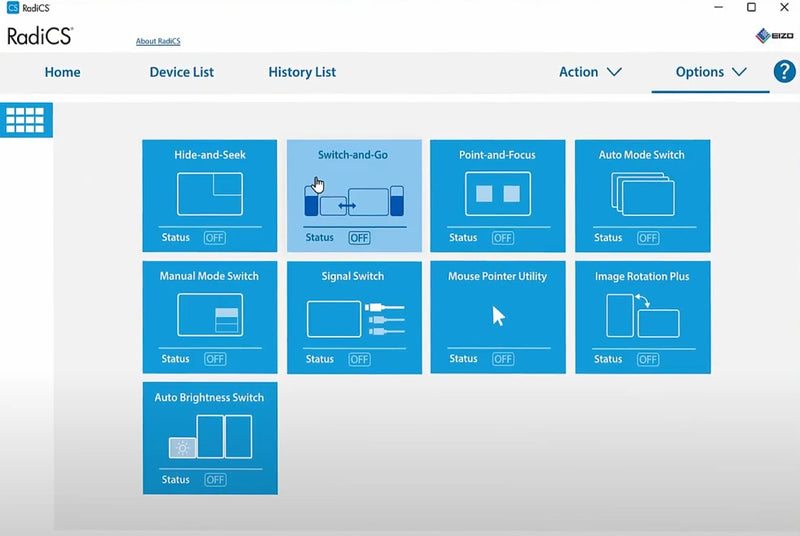

Τοποθετήστε γρήγορα περιοχές εστίασης

Με τη λειτουργία Point-and Focus, μπορείτε γρήγορα να επιλέξετε και να εστιάσετε περιοχές της ανησυχίας σας μόνο με το ποντίκι και το πληκτρολόγιό σας. Αλλάξτε τη φωτεινότητα και την κλίμακα των γκρι των συγκεκριμένων σημείων στην οθόνη για να διευκολύνετε την ερμηνεία.

Αναφορά γρήγορων πληροφοριών

Η λειτουργία απόκρυψης και αναζήτησης επιτρέπει στους χρήστες να κρύβουν εύκολα το παράθυρο PINP (Εικόνα στην εικόνα) που δεν χρησιμοποιείται και ανοίγει ξανά, όπως απαιτείται, μετακινώντας τον δρομέα του ποντικιού στην άκρη της οθόνης. Αυτό εξαλείφει την ανάγκη για μια επιπλέον οθόνη, ενώ παράλληλα επιτρέπει γρήγορη και αποτελεσματική προβολή αναφορών ή διαγραμμάτων ασθενών.

Χωροταξικό σύστημα εργασίας χωρίς φράγμα

Η συνάρτηση switch-and-go στο Radiforce RX1270 Eizo επιτρέπει την εναλλαγή USB μέσω της οθόνης, επιτρέποντας τη χρήση ενός ενιαίου πληκτρολογίου και ποντικιού σε δύο συνδεδεμένους υπολογιστές. Αυτό είναι βολικό για περιβάλλοντα διπλής οθόνων/υπολογιστή ή μεταβαλλόμενες εισόδους σε μία μόνο οθόνη που συνδέεται με δύο υπολογιστές.

Επιπλέον, μπορείτε να χρησιμοποιήσετε το Switch-and-Go με το Hide-and-Sek για να εμφανίσετε την οθόνη ενός φορητού υπολογιστή (συνδεδεμένο μέσω HDMI) ως ξεχωριστό παράθυρο στην οθόνη. Το παράθυρο μπορεί να κρυφτεί ή να εμφανίζεται στην εντολή χρησιμοποιώντας ένα μόνο ποντίκι και πληκτρολόγιο για να αποκτήσετε πρόσβαση σε περισσότερες πληροφορίες γρήγορα.

Καθώς οι περισσότεροι τρόποι εικόνας γίνονται ψηφιοποιημένοι, οι ακτινολόγοι βλέπουν μια αυξανόμενη ποσότητα πληροφοριών στις οθόνες τους. Η μοναδική τεχνολογία εργασίας και ροής του Eizo ανακουφίζει την πολυπλοκότητα της ροής εργασίας απεικόνισης με νέες λειτουργίες που αναπτύχθηκαν με τον ακτινολόγο. Οι χρήστες μπορούν να επωφεληθούν από τις λειτουργίες εργασίας και ροής με την οθόνη Radiforce και το λογισμικό LE Ladics.

Διαχειριστείτε τον αβίαστο ποιοτικό έλεγχο

Με το λογισμικό Radics LE (συμπεριλαμβανομένου) και τον ενσωματωμένο εμπρόσθιο αισθητήρα (IFS) ενσωματωμένο στην εμπρόσθια στεφάνη, μπορείτε εύκολα να βαθμονομήσετε στο DICOM Part 14 χωρίς να τοποθετήσετε και να αφαιρέσετε έναν εξωτερικό αισθητήρα.